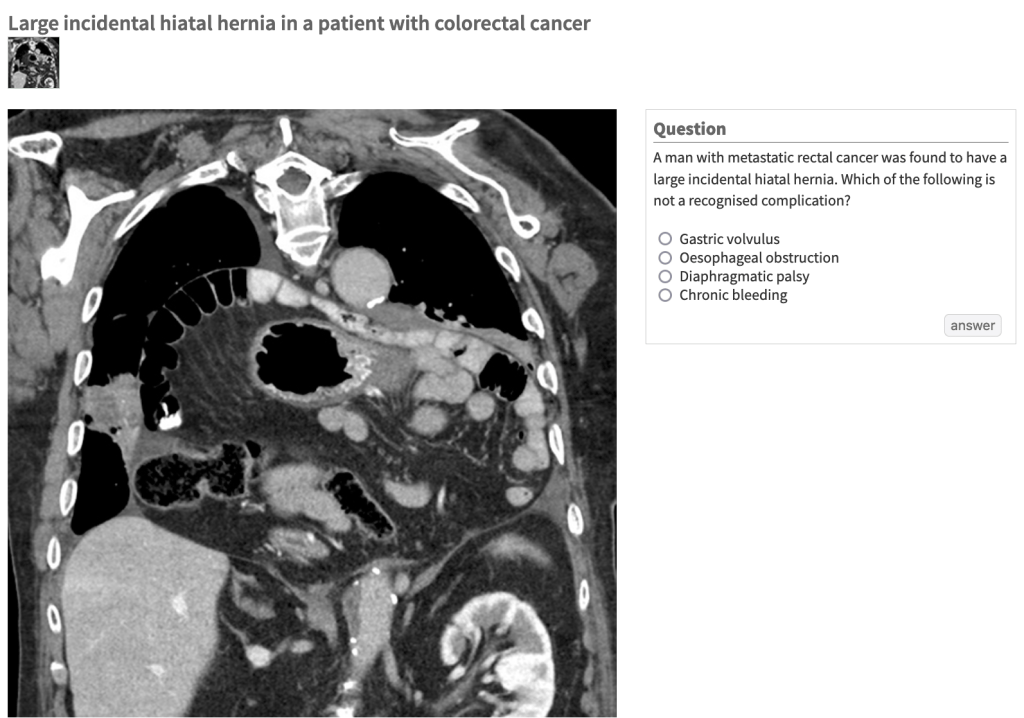

The Lancet: Picture Quiz

Another round of the Lancet picture quiz! 🙂